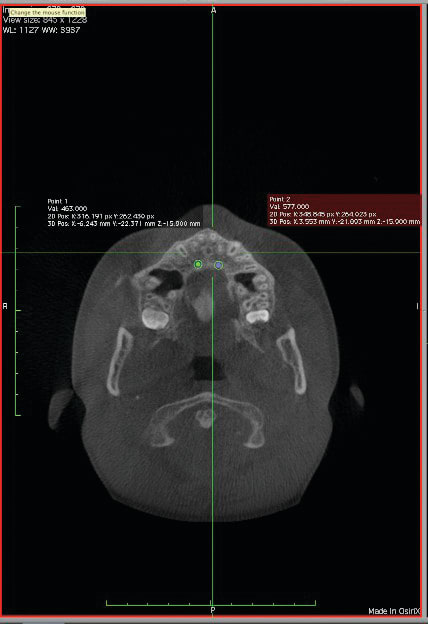

4. Any patient that will have a temporary skeletal anchorage device placed. Most clinicians that have become proficient and confident with the placement and use of TSADs place them on approximately 23% of the case treatment planned in their practices. When evaluating the placement site in all three planes of space, the clinician can become very exact with locating structures that should be avoided. More TSADs are being placed in the infazygomatic area. A 3D image is the best way to locate the optimal area of placement for stability in this area. See Figure 13 and note the thickness of the bone in the infrazygomatic crest. Compare the thickness of the bone in Figure 14. The bone in this figure demonstrates bone that is too thin for placement of the TSADs. More TSADs are being placed in to palatal approach. TSADs placed in the premaxilla are an area of placement that is vitally important to visualize the anatomy in this area. One should consider the thickness of bone in this area to avoid the tips of the TSADS from penetrating the nasal cavity and to avoid the roots of the teeth in this area. See Figure 15 through Figure 17. When skillfully placed in adequate bone, the use of TSADS certainly allows orthodontist to treat their patients more consistently and predictably. The use of 3D imaging aids the clinician in the placement and use of the TSADs.